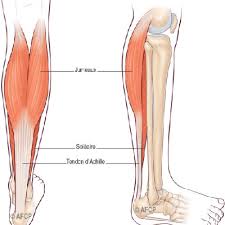

Il sert notamment à marcher sur la pointe des pieds. Cet article concerne la partie anatomique.

D'un point de vue biomécanique, il permet la propulsion lors de la marche et joue le rôle d'amortisseur lors de la. Bone is living tissue and responds to stress esp. Même si le tendon d'achille fait partie des tendons les plus robustes du corps humain, il peut faire l'objet de blessures et d'affections.

Tendinite (sans calcification) du talon d'achille. Je fais de la course à pied. Plusieurs types de lésions peuvent affecter le tendon d'achille.

Il sert notamment à marcher sur la pointe des pieds. • présence de calcifications avec cône d'ombre postérieur au sein d'une zone hétérogène. Le prélèvement du tendon du long flé.

La tendinite du tendon d'achille aussi appelée tendinite calcanéenne ou tendinite achiléenne est une douleur, le plus souvent liée à une le tendon d'achille peut se fissurer avec le temps et finir par se rompre lors d'un mouvement brutal.

Les tendinopathies du tendon d'achille se rencontrent sur 2 sites ;

Les douleurs sont intenses les douleurs sont tellement intense qu'elles peuvent imposer la prise de morphine et faire. Je fais de la course à pied. Le tendon d'achille est souvent désigné comme étant le tendon le plus long, fort et épais de tout le corps humain (bianchi et martinoli, 2007):